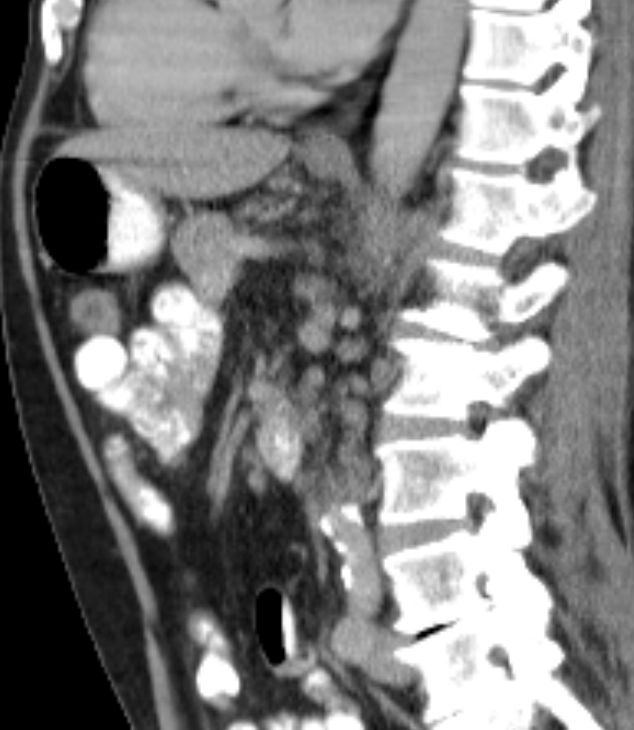

| Diagnostik | 68jähriger Mann mit B-Symptomatik und Splenomegalie.